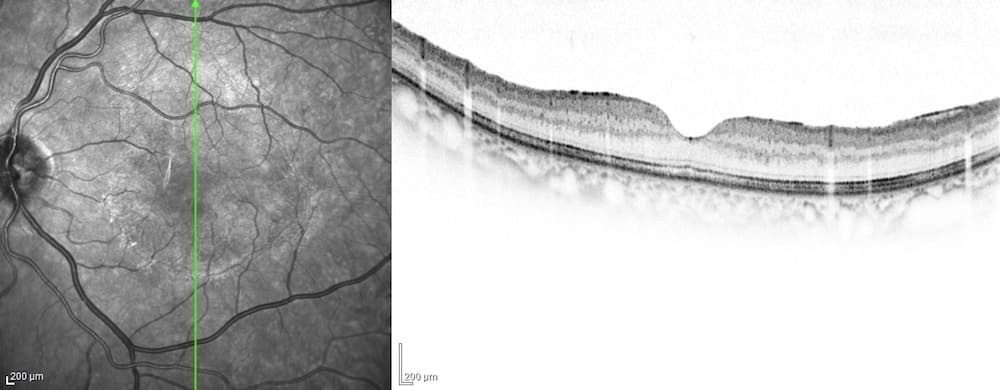

網膜静脈閉塞症(もうまくじょうみゃくへいそくしょう)

網膜の静脈が詰まって血液が流れなくなる病気です。高血圧や動脈硬化、糖尿病のある方に多いとされています。静脈が詰まると網膜の血流が悪くなり、閉塞範囲が広くなると新生血管という悪い血管が生じます。新生血管からの出血により硝子体の混濁が強くなると

硝子体手術が必要となることが多いです。